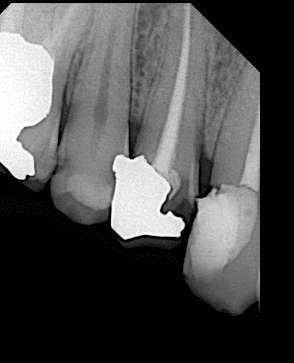

Pre-operative x ray showing the bad situation of the tooth